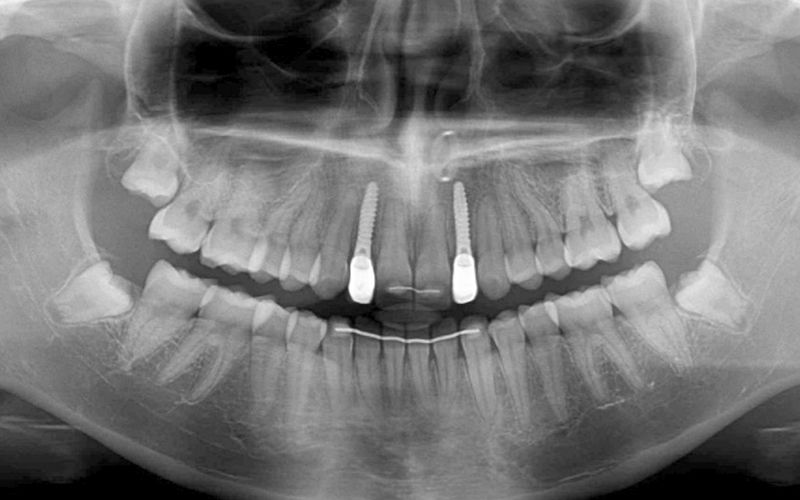

Paciente mujer de 16 años acude a la clínica por motivo de agenesia de los incisivos laterales superiores 12 y 22. La paciente no presentaba antecedentes médicos de interés y a la exploración clínica y radiográfica se observó que gozaba de una excelente salud oral. Derivamos a la ortodoncista que, tras un estudio pertinente, inició un tratamiento con brackets para tratar de lograr el espacio máximo entre los centrales y caninos con el propósito de colocar dos implantes a futuro.

Al cabo de todo este tiempo se realizó un CBCT maxilar para iniciar la planificación de la cirugía de colocación de dos implantes en posición de 12 y 22. Durante el análisis de las imágenes radiográficas, tal y como indican las mediciones que se realizaron, se observó una limitación de espacio en sentido mesio-distal entre 11 – 13 y 21 – 23, que iba a impedir la colocación de dos implantes estándar de 3.3 mm de diámetro.

Dadas las circunstancias y para buscar una resolución óptima del caso, se decidió utilizar implantes Biomimetic Pearl de diámetro reducido de 2.8 mm de Avinent Implant System. Estos mini-implantes disponen de una línea protésica para rehabilitaciones unitarias y, dentro de su amplia gama, encontramos el que se ajustaba mejor a las exigencias del caso, permitiendo mantener perfectamente la distribución de espacio para poder respetar la biología de la rehabilitación.

Se llevó a cabo la cirugía de colocación simultanea de los implantes Pearl de 2.8 x 13 mm en posición de 12 y 22 siguiendo el protocolo indicado por la casa comercial. Estos fueron colocados con éxito a pesar de que las condiciones anatómicas no eran muy ventajosas, consiguiendo 30 Ncm de torque en ambos.